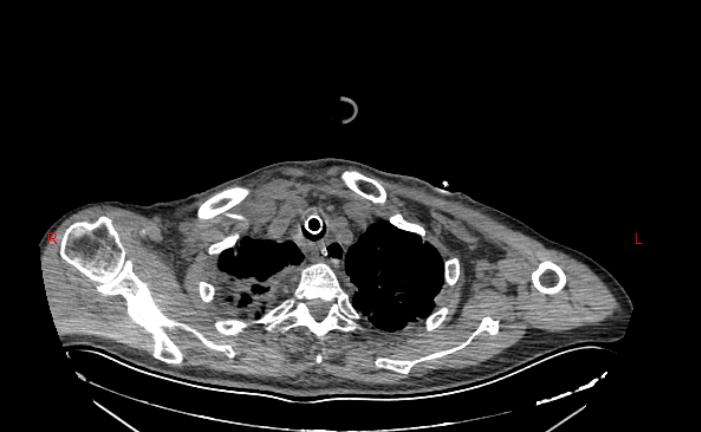

7月,贾先生因车祸导致全身多发伤急诊入院,诊断结果触目惊心:重症肺炎、脓毒性休克、I型呼吸衰竭、右侧胫腓骨下端开放性粉碎性骨折、骨盆多发骨折、左侧多发肋骨骨折、创伤性硬膜下出血等13项严重损伤,高龄、重症、多发伤的叠加让救治难度陡增。重症医学科第一时间启动紧急救治,抗感染、抗休克、呼吸机支持等一系列关键措施精准落地,为患者筑牢生命防线。待病情相对稳定后,患者转入专科进一步治疗,开启了分阶段的精准修复之路。

从7月29日的“右侧胫腓骨下端开放性骨折闭合复位内固定术+外固定术”,到9月2日的“右下肢清创术+局部转移皮瓣修复术+取皮植皮术”,再到9月29日的“右胫骨粉碎性骨折闭合复位+有限切开髓内针内固定术”,三次关键手术环环相扣、精准施策。术后,医疗团队持续给予抗感染、消肿止痛、抗凝、促骨折愈合等综合治疗,护理团队则从伤口护理、肢体功能训练到营养支持全程精细化照护,用专业与温暖陪伴患者度过艰难的康复期。